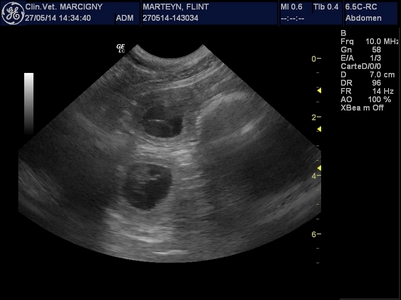

Le mariage de Genkini et Flint'on va porter ses fruits ! De belles petites "bulles de bonheur" nous ont fait coucou lors de l'échographie :-)